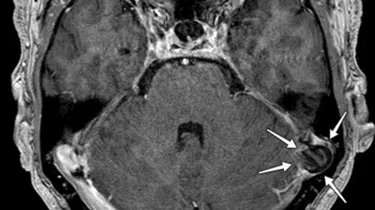

Specialeansvarlig overlæge Søren Larsen underviste yngre ortopædkirurger i store håndskader og replantation